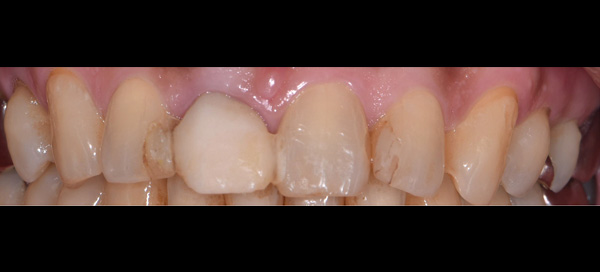

| 年代・性別 | 50代 男性 |

|---|---|

| 主訴 | 前医で前歯を抜かなければならないがインプラントはできないと言われた |

| 治療期間 | 約12ヶ月 |

| 費用 | 600,000円 |

| 治療内容 | インプラント、骨造成、結合組織移植、セラミック修復 |

| 治療に伴うリスク | インプラント周囲炎 セラミックの破折、脱離 |